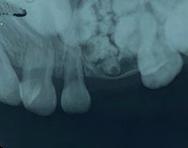

Figura 2. A. Radiografía periapical donde se observa la lesión del odontoma compuesto a nivel del maxilar superior izquierdo. B. Ortopantomografía que revela una lesión radiolúcida unilocular bien definida, con manchas de focos radiopacos, asociada con el canino superior izquierdo temporal impactado de la maxila.

Figura 1. Fotografía de la zona de la lesión en la exploración clínica inicial. Se observa ausencia del canino superior izquierdo, ensanchamiento de la cortical vestibular y aumento de volumen.

A B

El examen clínico reveló un aumento de volumen en la zona de órganos dentarios 63-65 que se extendía al seno maxilar, con desplazamiento de cortical vestibular, sin perforación ni cambio de color en la mucosa, de estructura uniforme bien delimitada. (Figura 1). En el examen radiográfico se observó la expansión de la cortical, con la presencia de múltiples dentículos. Desplazamiento del órgano

175. Marzo 2023 33 Tumores odontogénicos mixtos

dentario 63 hacia el seno maxilar (Figura 2).